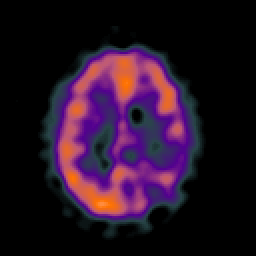

SPECT TC Study #5 -- Slice #35

[Home][Help][Clinical][Tour 1][Tour 2][Tour 3] Slice 35